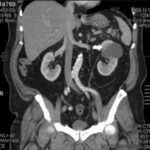

La Categoría III muestra engrosamientos lisos o irregulares de la pared o de los septos intra quísticos y existencia de realce medible en TC y RMI. Se consideran masas indeterminadas y precisan de primera instancia cirugía, nefrectomía parcial o ablación por radiofrecuencia, salvo contraindicaciones clínicas.(19, 21) Aproximadamente el 40%-60% son lesiones malignas (carcinomas renal quístico), siendo el restante benignas, que incluyen quistes hemorrágicos, infectados crónicos o calcificaciones parietales, nefrona quístico multiloculado, quistes multilobulados, quistes con tabiques complejos, etc. (Anexos 9 y 10).

La Categoría IV presenta captación de un componente sólido intra quístico, muestra realces nodulares fuera de la pared y de los septos interpuestos en el área quística compleja, calcificaciones gruesas, vascularizadas con un importante realce con contraste yodado IV. En realidad, son lesiones malignas con componente quístico. Se trata de neoplasias quísticas, y precisan cirugía y estadificación.(19, 21) (Anexos 11 y 12).